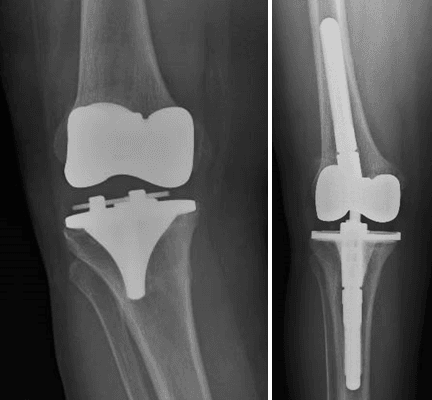

L’intervento chirurgico di revisione protesica si attua nel caso di fallimento dell’impianto primario. La revisione può essere totale (quando vengono sostituite tutte le componenti) o parziale (quando vengono sostituite solo alcune componenti), a seconda dell’entità e del tipo di problema riscontrato.

La revisione protesica rappresenta una vera e propria sfida per il Chirurgo Ortopedico, soprattutto in quei casi gravati da importante perdita del bone stock, da deficit dei tessuti molli periarticolari o in presenza di alterazioni del trofismo cutaneo, talvolta con perdita severa di sostanza, in esiti di plurimi interventi chirurgici.

Grazie ad un’esperienza chirurgica decennale nel trattamento e nella gestione di casi difficili di revisione protesica, presso il nostro centro di Chirurgia Protesica pianifichiamo accuratamente gli interventi ricostruttivi protesici, avvalendoci delle più innovative tecniche e metodiche chirurgiche (impianti protesici su misura quando necessari), ponendo particolare attenzione nell’utilizzo di materiali protesici biocompatibili che garantiscono un’ottimale osteointegrazione ed una resistenza all’usura sempre maggiore.